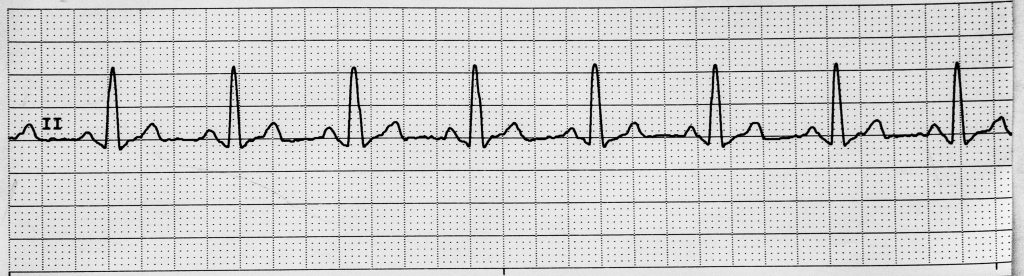

Rhythm #2 of 20